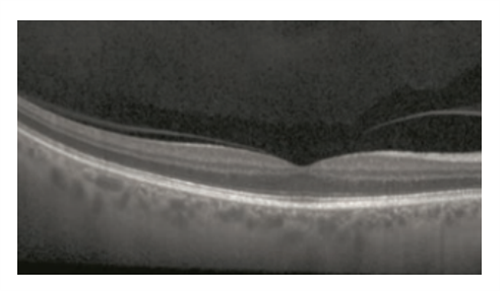

那天接女儿放学路过一个文具摊,各色文具琳琅满目,各种笔总是让人好奇,我拿起一支长得很像眼科医生平时用的手电筒的笔,上面有两个按钮,按下其中一个按钮发出的真的是手电筒的那种弥散的灯光,没想到文具店也卖手电笔!我的眼科检查手电笔正好坏了,可以顺便买一个呀!正这么想着,我下意识地按下另外一个按钮,是一束正对着我的眼睛的蓝紫色强光,确切地说是正对着右眼的黄斑,糟糕!是激光笔!虽然从激光照射到我反应过来的时间不足1秒钟,但当我闭上左眼,右眼可以感觉到眼前中央是一个豆粒大小的圆形暗斑,暗斑中央是看不清楚的,周边的视野都是没问题的,顿时我的脑海中闪现出激光笔照射后黄斑光损伤、甚至是黄斑裂孔的图像(图1示正常黄斑,图2示黄斑外层关键细胞的断裂,图3示激光笔照射后黄斑裂孔),要知道黄斑可是人的眼睛看东西非常非常关键的部位,我的心中充满了懊悔,如果我的黄斑真的损伤了怎么办!黄斑裂孔后的世界将永远是视野中间的暗斑,想看哪里哪里不清楚,想想都让人难过!

图1 正常黄斑